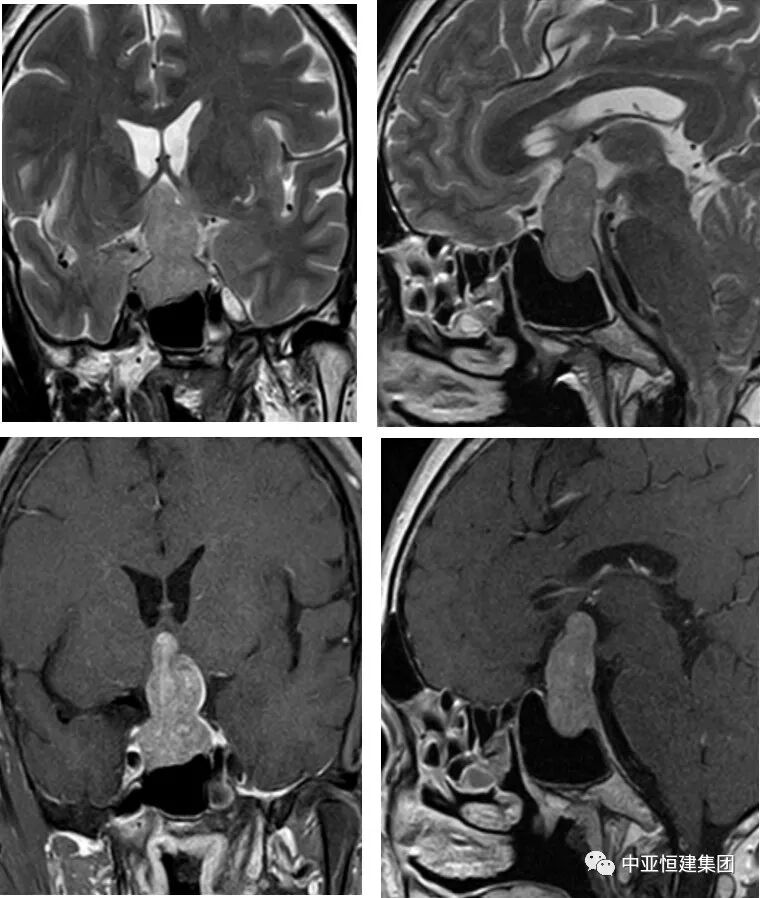

MRI增强目前是垂体瘤诊断主要检查方式之一,垂体微腺瘤一般用冠状面和矢状面薄层,包括 T1 和 T2 图像。

T1 微腺瘤呈低信号,多位于垂体一侧,T2微腺瘤呈高信号或等信号。动态增强扫描,肿瘤信号早期低于垂体,后期高于垂体。

垂体大腺瘤肿瘤呈圆形,也可呈分叶或不规则形,腺瘤实质部分呈等信号,当合并囊变坏死、出血或钙化时呈混杂信号,增强扫描实质部分强化明显,囊变坏死、出血或钙化不强化。

冠状扫描显示肿瘤呈哑铃状,这是由于肿瘤伸于鞍上,中部受鞍隔束缚之故。肿瘤向上使鞍上池闭塞,视交叉上抬,向旁侧压迫海绵窦延伸至颅中窝,向后可压迫脑干,向下可扩大蝶鞍、突入蝶窦。肿瘤向鞍旁生长,可将明显强化的颈内动脉向外推移甚至包裹,偶尔可引起颈内动脉闭塞。

MRI 诊断垂体肿瘤可靠,95% 以上的垂体肿瘤可做出诊断,但难于做出组织学诊断。大的垂体肿瘤常见蝶鞍增大和鞍内及向鞍外延伸、边界清楚的肿块,CT 上为略高密度;MRI 上,T1WI 为等信号,T2WI 为高信号,有明显均匀强化。依上述表现多可做出诊断。垂体微腺瘤的诊断主要靠 MRI,直接征象是 T1WI 上垂体内的低信号病灶,增强检查更为明确。